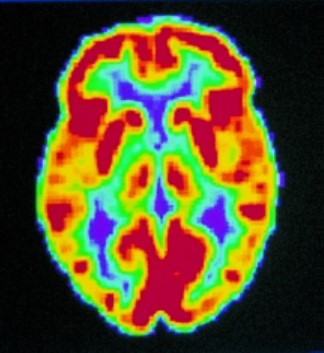

Today, scientists are able to monitor living brains thanks to advanced imaging techniques. This allows us to understand how brain function changes with aging or disease. [55]

One of these techniques is:

🧠 Positron Emission Tomography (PET Scan)

- It measures blood flow and glucose metabolism within the brain.

- When neurons in an area of the brain become active, blood flow and metabolism there increase.

- PET scans show this increase in red and yellow colors.

- Blue and black tones indicate areas with low or no activity.

With these scans, we can see what is happening in a person's brain when they are sleeping, resting, or doing a mental task. It is also possible to monitor neurotransmitters (chemical transporters between nerve cells) such as dopamine and serotonin. These substances can change with age, disease or medication. [55]

Figure 1 shows the PET Scan of the Normal Brain, and Figure 2 shows the PET Scan of the Alzheimer's Disease Brain.

Figure 1: PET Scan of the Normal Brain [55].